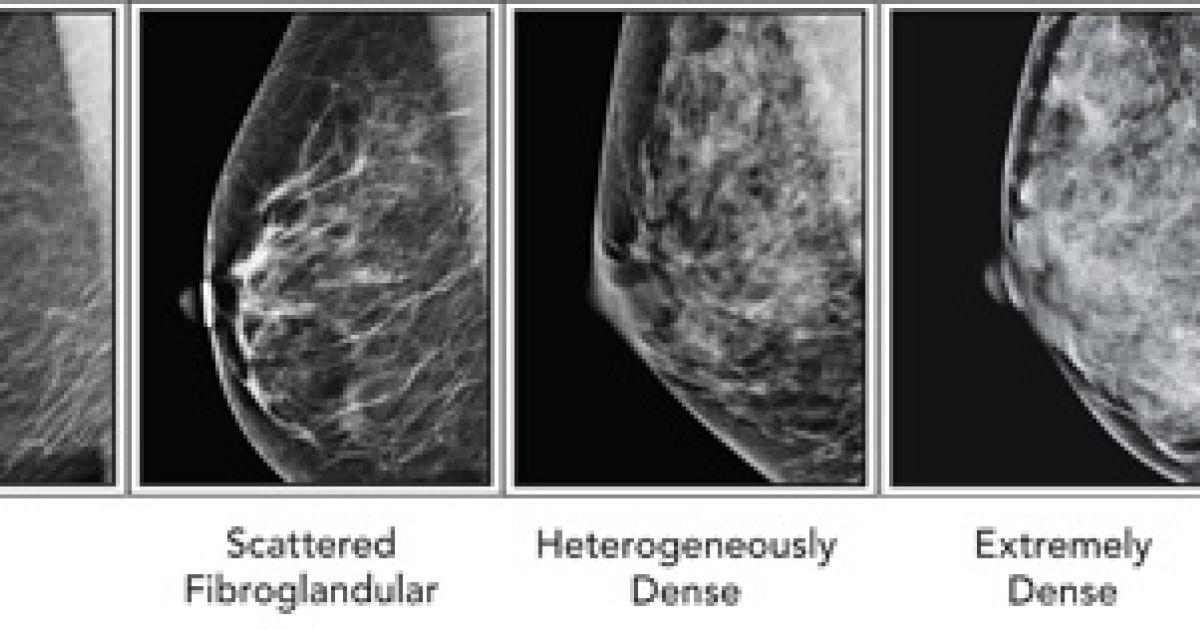

Although it is possible for some physicians to separate a very dense breast from a non-dense breast by a physical breast exam, the level of density is not possible to feel by touch. For that, physicians rely on mammography. Radiologists use a four category classification scheme when assessing the breast tissue on a mammogram called the Breast Imaging Reporting and Data System (BI-RADS).

The four classes, as indicated on the picture below, from left to right, are:

- Mostly fatty: The breasts are made up of mostly fat and contain little fibrous and glandular tissue. The mammogram would likely show anything that was abnormal.

- Scattered density: The breasts have quite a bit of fat, but there are a few areas of fibrous and glandular tissue.

- Consistent density: The breasts have many areas of fibrous and glandular tissue that are evenly distributed through the breasts. This can make it hard to see small masses in the breast.

- Extremely dense: The breasts have a lot of fibrous and glandular tissue. This may make it hard to see a cancer on a mammogram because the cancer can blend in with the normal tissue. (1)

In the above picture of the BI-RADS classification, the difference between dense and non-dense breasts seems clear. Technically, the last two of the four categories would fall under the umbrella category of "dense breasts." However, a recent study published in the Annals of Internal Medicine, through the NIH / National Cancer Institute, suggests that the classification of breasts as dense actually varies tremendously between physicians.